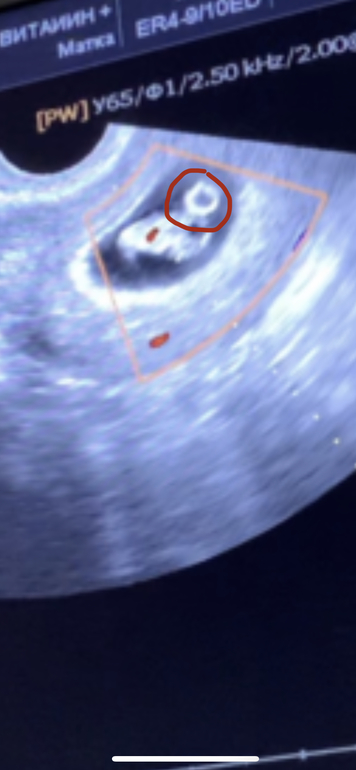

Сделала узи 8+6 недель

Она крутила крутила я вообще не поняла где ребёнок но она сказала все хорошо, вернее я поняла где ребёнок но там ещё рядом какой то круг она сказала это головной мозг и тогда я поняла что я ничего не поняла))

Круг это Желточный мешочек, ребёнок питается от него сейчас)

Вот это Мешочек да ?